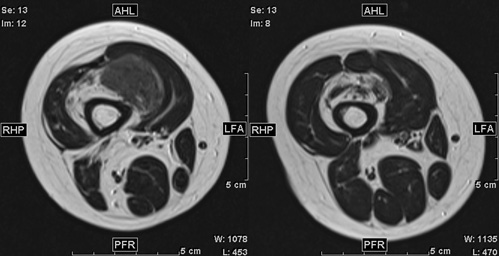

男児

生下時からの右膝腫大

5歳:腫瘤周囲脂肪の増生と大腿四頭筋の萎縮・脂肪変性点状石灰化

15歳:大腿四頭筋腱や膝蓋腱に沿って広がる境界明瞭な腫瘤